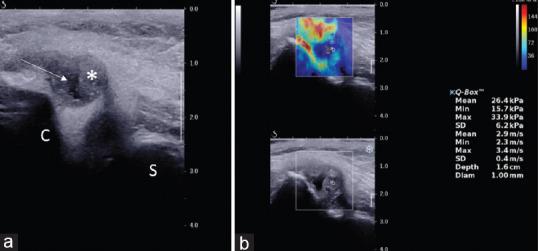

The prospective study was performed on Supersonic Imagine Aixplorer Ultrasound (USG) machine using a linear array probe SL10-2 (2-10 MHz). A total of 29 participants, 15 of RA (ACR/EULAR criteria) and 14 of proven TB arthritis were included. Region of interest of 1 mm was applied on the hypertrophied synovium and quantitative SWE data in form of elasticity (kPa) and velocity (m/s) were measured. Discrete categorical data were presented as n (%). Mean values were recorded along with standard deviation and the range of values. To find a maximal cutoff value of elasticity and velocity - receiver operating characteristic curve were plotted.

The mean elasticity and velocity values were 54.81 ± 10.6 kPa and 4.2 m/s ± 0.42 for RA and 37 ± 10 kPa and 3.4 ± 0.47 m/s for TB group. Significant difference ( < 0.001) was seen in elastic modulus values between rheumatoid and TB group with cutoff of 43.6 kPa to differentiate the two groups (sensitivity - 86.7% and specificity - 80%). Similar significant ( < 0.001) results were seen with velocity values, with cutoff of 3.76 m/s (sensitivity - 86.7% and specificity - 80%).

SWE shows the potential to be a useful adjunct to gray scale and color Doppler USG in differentiating various arthritis on the basis of elastic properties of the synovium. Elastic modulus and velocity are useful SWE quantitative parameters for synovial evaluation and can differentiate RA and TB arthritis.